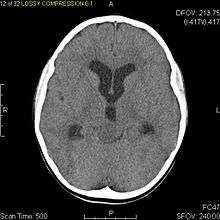

Pilocytic astrocytoma or juvenile pilocytic astrocytoma or cystic cerebellar astrocytoma (and its variant juvenile pilomyxoid astrocytoma) is a brain tumor that occurs more often in children and young adults (in the first 20 years of life). They usually arise in the cerebellum, near the brainstem, in the hypothalamic region, or the optic chiasm, but they may occur in any area where astrocytes are present, including the cerebral hemispheres and the spinal cord. These tumors are usually slow growing and benign.[1] The neoplasms are associated with the formation of a single (or multiple) cyst(s), and can become very large.

Pilocytic astrocytomas are often cystic, and, if solid, tend to be well-circumscribed. It is characteristically easily seen on CT scans and MRI.

Usually—depending on the interview of the patient and after a clinical exam which includes a neurological exam, and an ophthalmological exam—a CT scan and or MRI scan will be performed. A special dye may be injected into a vein before these scans to provide contrast and make tumors easier to identify. The neoplasm will be clearly visible.